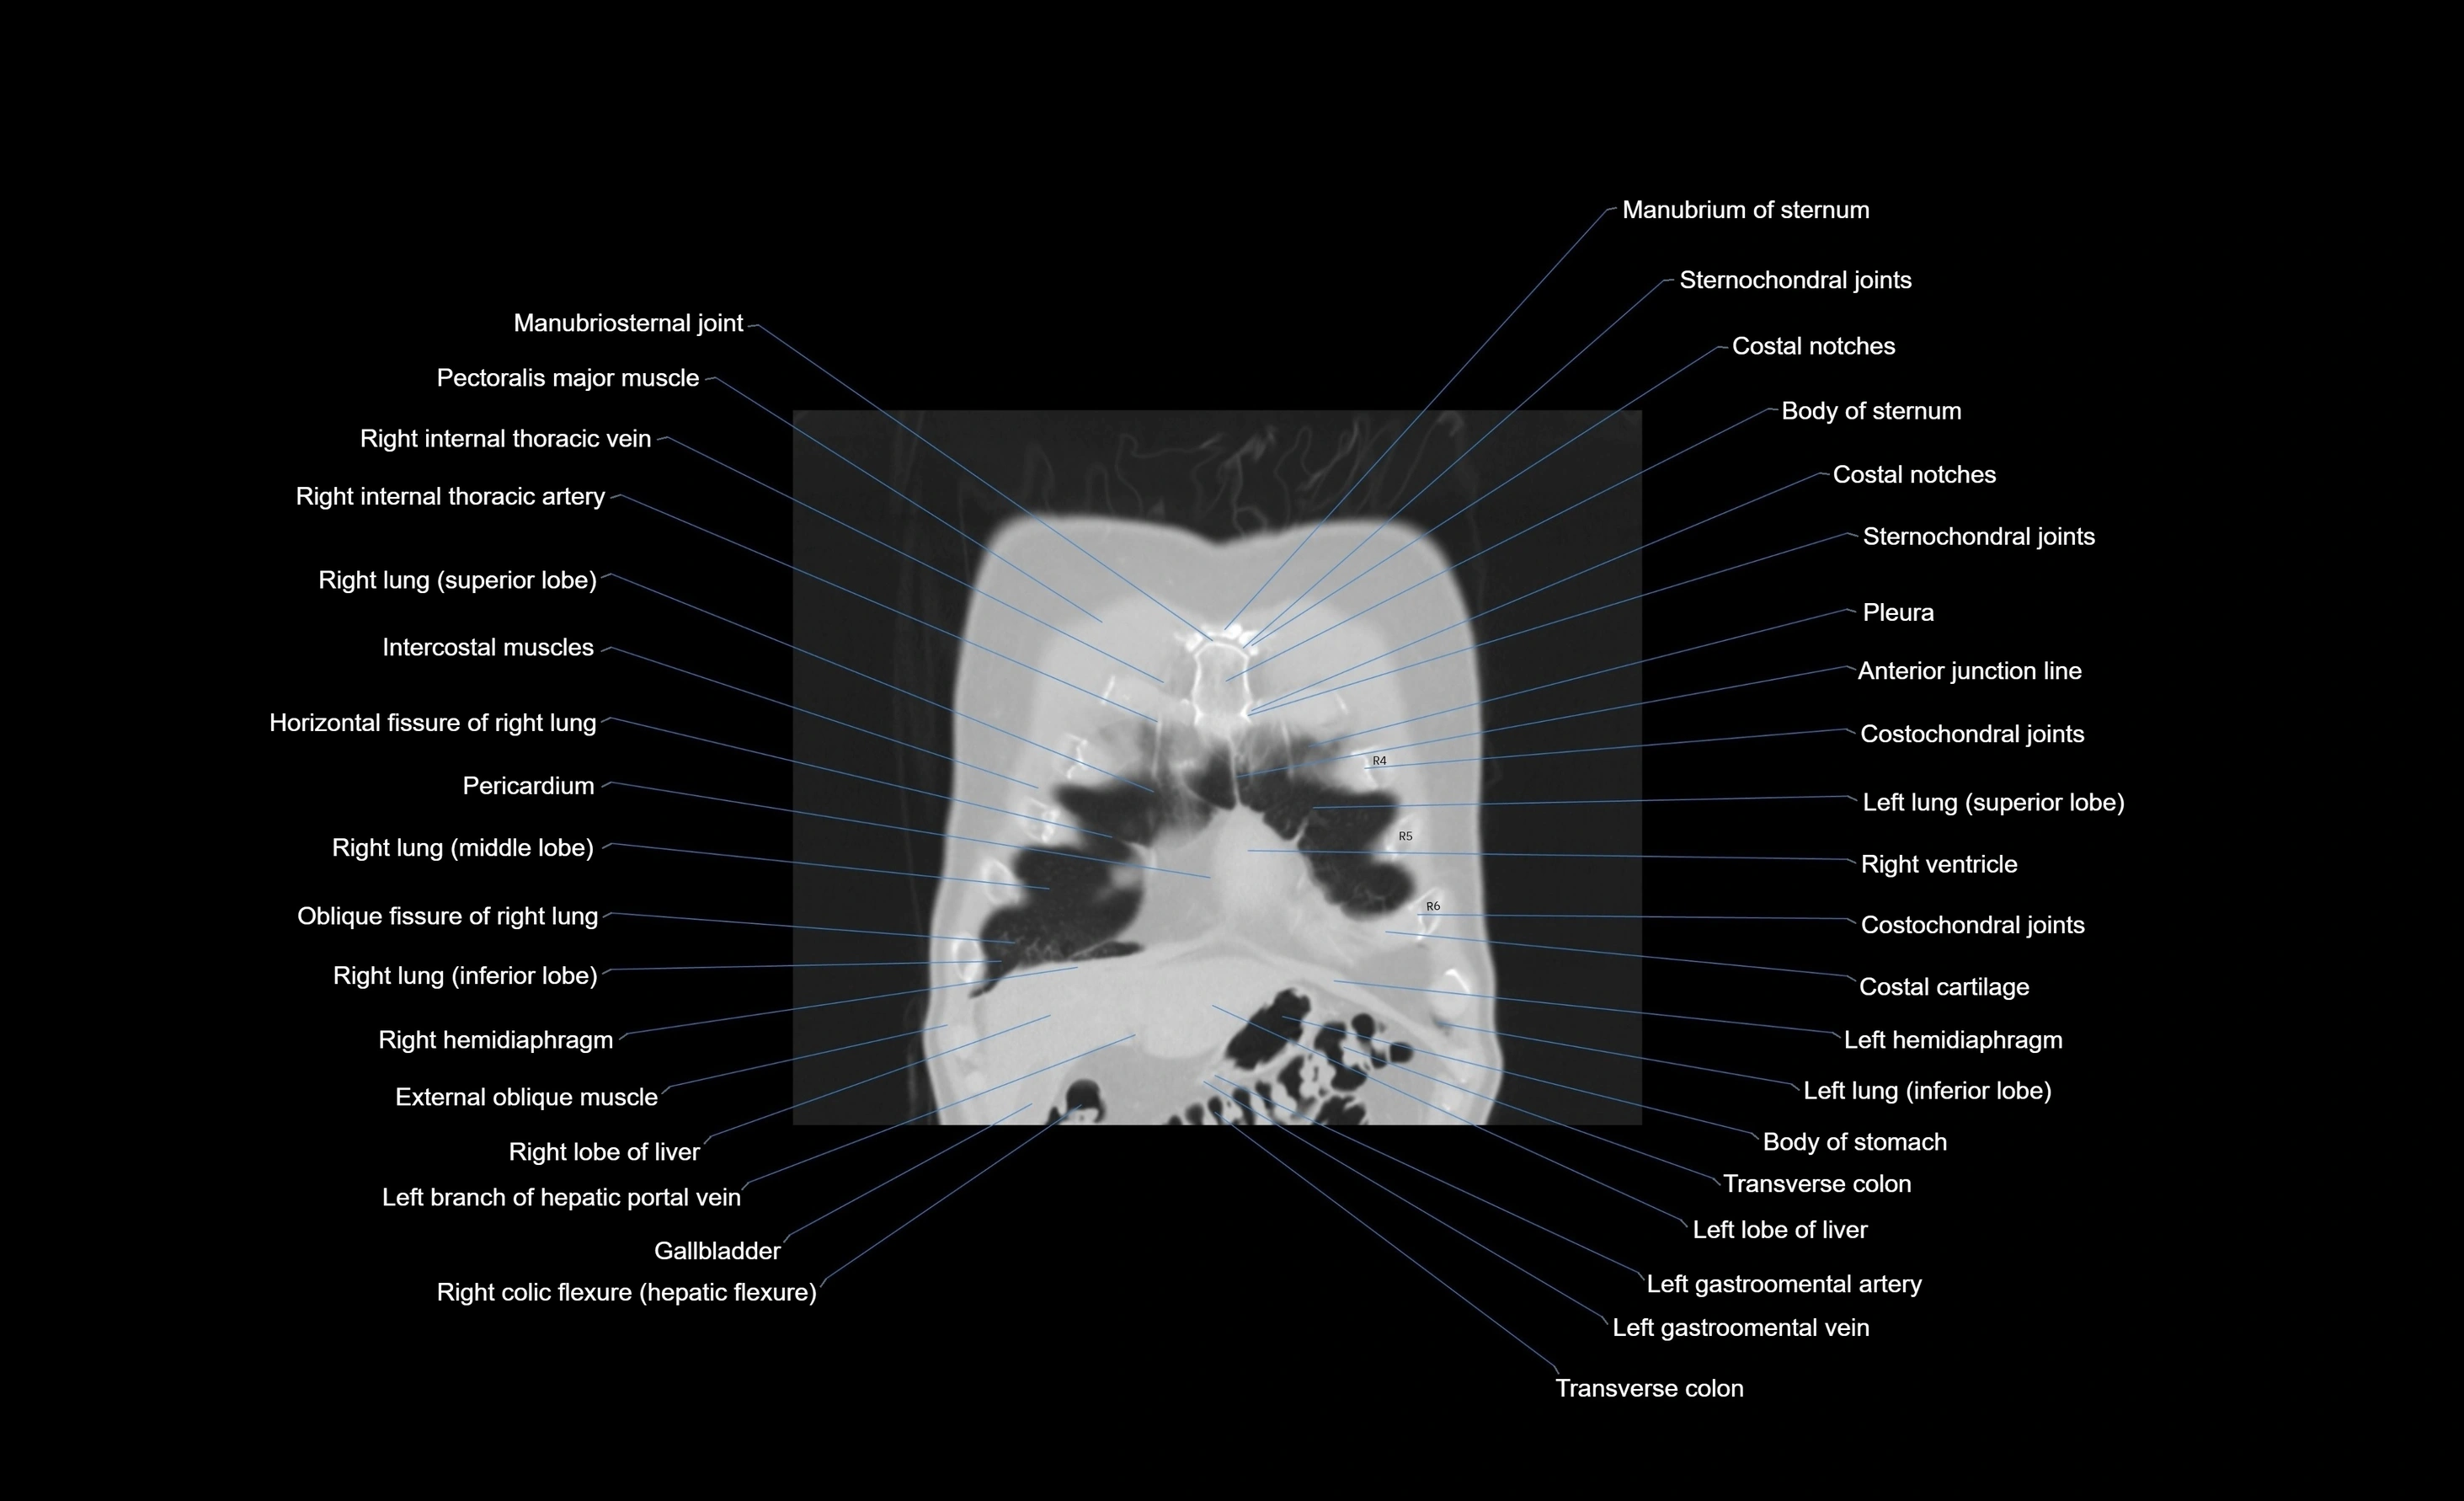

- External oblique muscle

- Gallbladder

- Hepatic portal vein

- Left hemidiaphragm

- Left lobe of liver

- Right hemidiaphragm

- Right lobe of liver

- Transverse colon